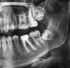

Weisheitszahn

Entfernung

Wenn Weisheitszähne Schmerzen verursachen oder Fehlstellungen begünstigen, entfernen wir sie kontrolliert und gewebeschonend. Die Planung erfolgt individuell – für einen sicheren Eingriff und eine zügige Heilung.